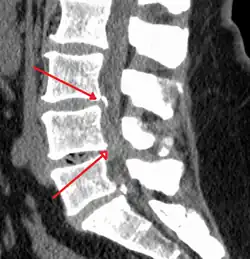

Moderate to severe spinal stenosis at the levels of L3/4 and L4/5

The diagnosis of spinal stenosis involves a complete evaluation of the spine. The process usually begins with a medical history and physical examination. X-ray and MRI scans are typically used to determine the extent and location of the nerve compression.